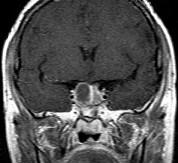

问题 女,45岁,垂体瘤术后7年,2个月前开始诉头痛,视物多模糊,请根据所提供图像,选择最可能的诊断()

选项 A.垂体瘤术后改变 B.垂体瘤术后恶变 C.垂体瘤术后出血 D.(垂体)嫌色细胞腺瘤(复发性) E.颅咽管瘤

答案 D